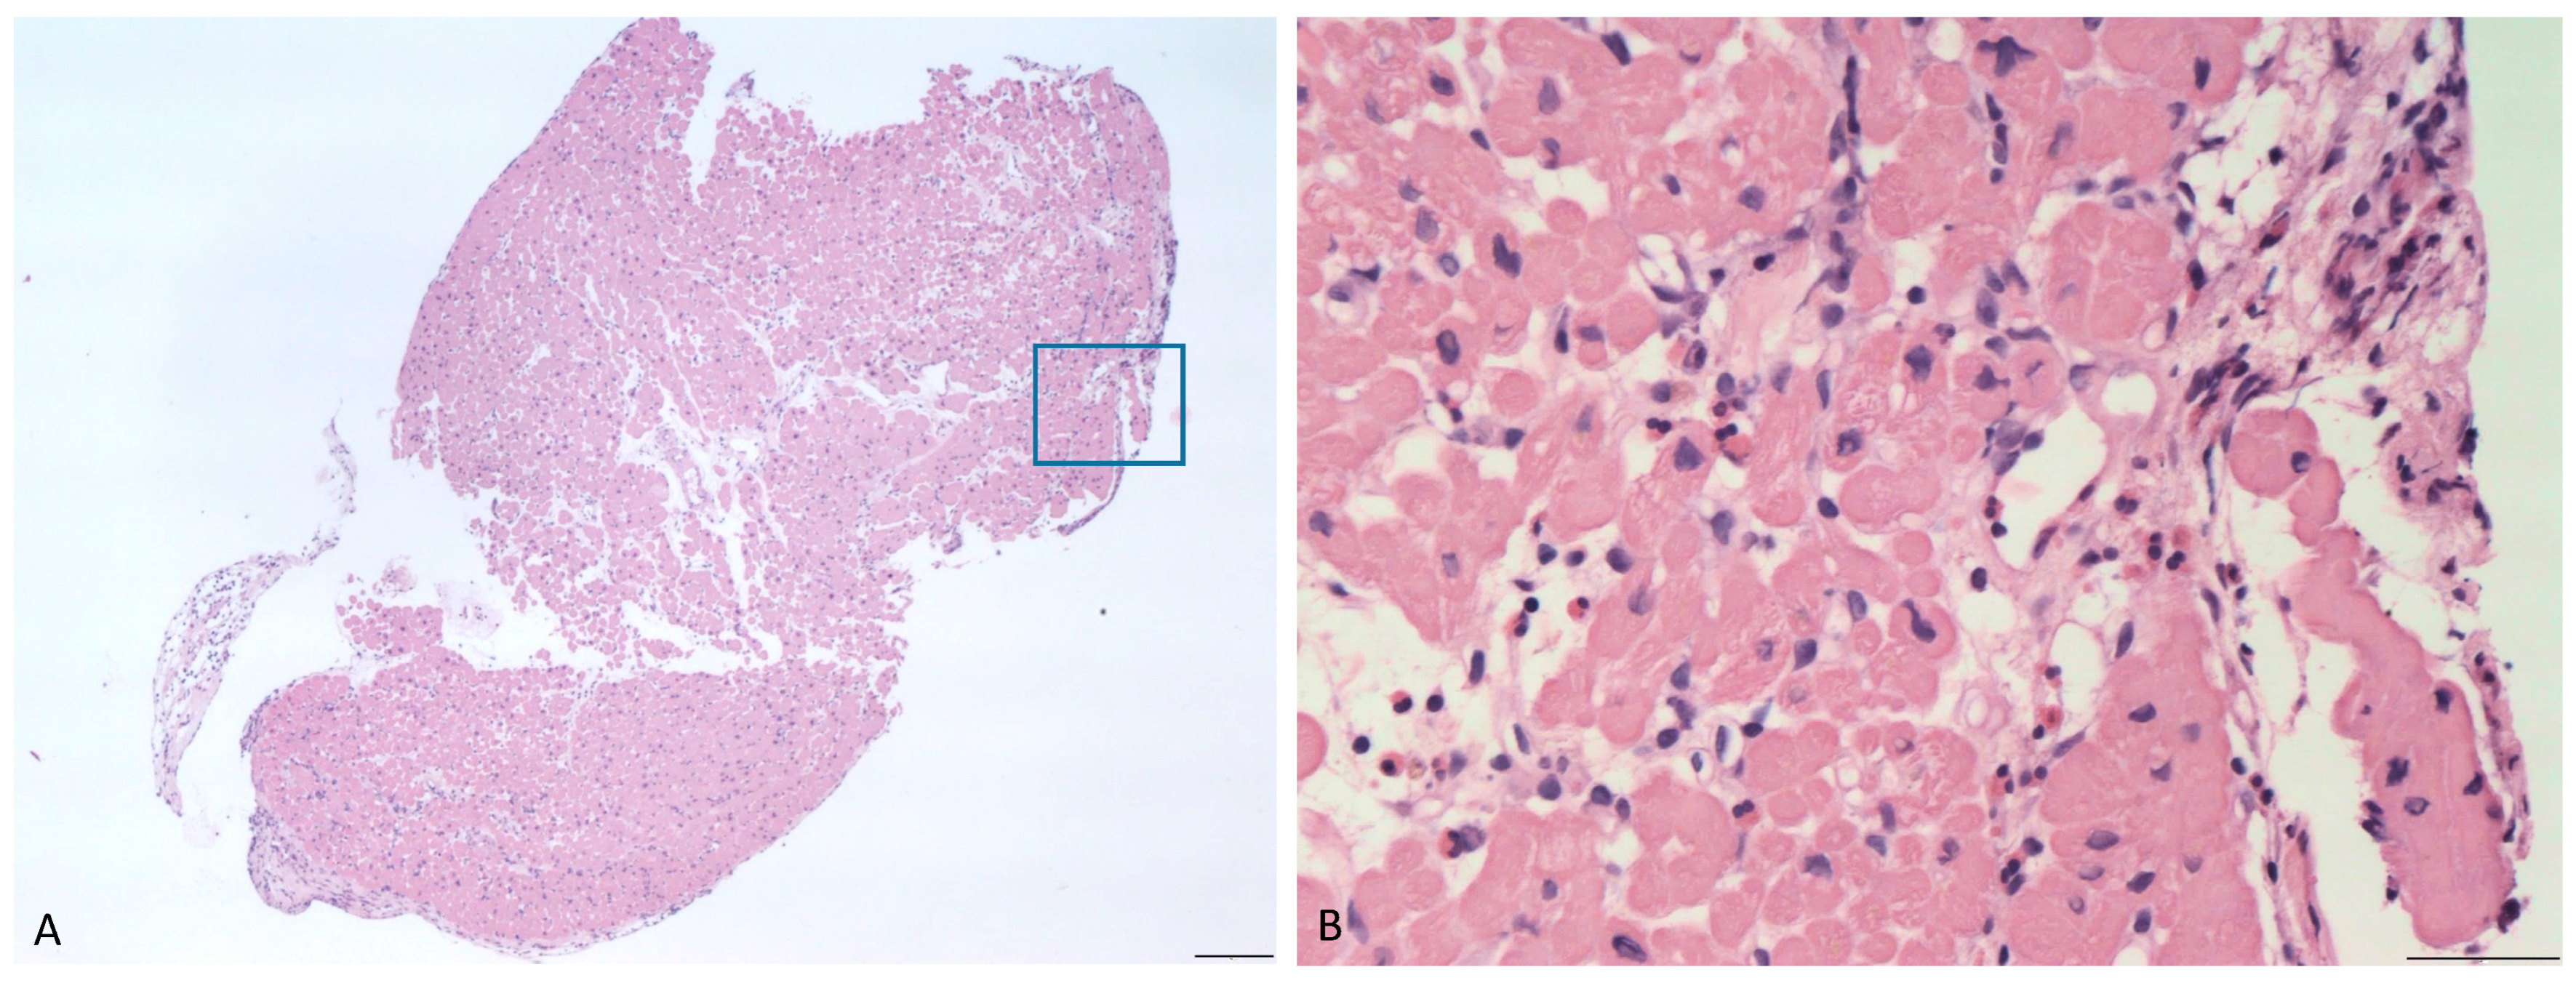

2. Case Presentation